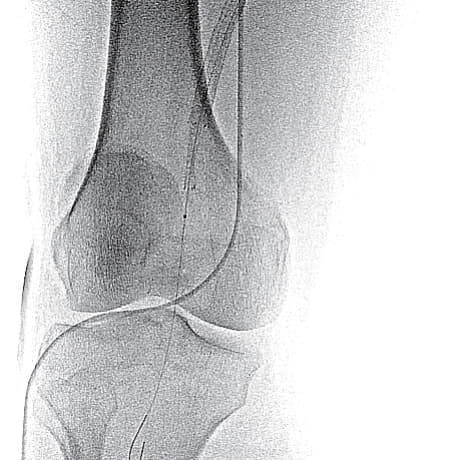

- SFA起始部にわずかなstumpを認め、膝窩動脈のP1-segmentまで連続する閉塞病変あり(図1)